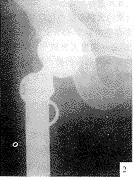

例1,男,65岁,右髋疼痛1年。外伤后肿痛、活动受限3天入院。体检:右髋轻度肿胀,无红肿,右下肢屈曲、外旋,短缩畸形,短缩1.5 cm,髋前外侧压痛,大转子叩击痛(+),髋关节活动受限。X线片(图1)示右股骨转子轻度膨胀,皮质变薄,呈蜂窝状骨破坏,内有不规则小囊样透亮灶,间隔骨嵴增生硬化伴病理骨折。诊断:右股骨转子间病理性骨折,骨转移癌?术中见肿瘤为囊性溶骨破坏,内有暗红色肉芽组织。手术行股骨上段瘤段切除,特制半髋假体置换术(图2)。病理诊断:右股骨转子间造釉细胞瘤。病理见骨的纤维间质中分布一些上皮样细胞岛,细胞被纤维组织分隔或包绕成片状、巢状,多数区域细胞形态似鳞状细胞,少部分区域似基底细胞。

图1 例1长骨造釉细胞瘤术前

图2 例1长骨造釉细胞瘤术后